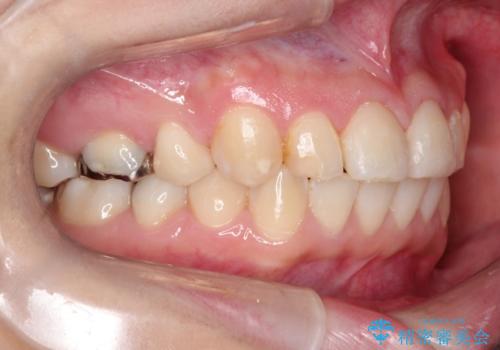

【ワイヤー矯正】前歯が出てるのをなおしたい。

- 矯正装置

- 審美装置

- 前歯の凸凹を主訴に来院されました。

見た目だけではなくかみ合わせも良くなったと満足して頂きました。

治療後は見た目だけでなく、噛みやすくなったと満足していただけました。